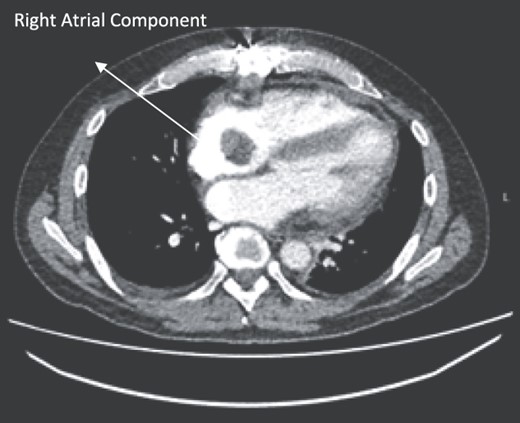

A 52-year-old gentleman was admitted to a district general hospital for shortness of breath causing type 1 respiratory failure with oxygen saturations of <90% despite high flow oxygen. His past medical history was unremarkable, and he was usually fit and well. A CT Pulmonary Angiogram (CTPA) was undertaken, which showed a heterogeneous oval-shaped lesion measuring 15 × 9 × 14 cm3 between the heart and the diaphragm, with a median attenuation of 35 HU and no enhancement during the arterial phase. Further solid lesions of 14 mm in the right lower lobe and 5 mm in the right upper lobe raised the suspicion of a primary cardiac sarcoma with pulmonary metastasis. This is shown in Fig. 1. Subsequent urgent CT staging (Fig. 2) was undertaken, which confirmed an indeterminate space occupying the inferior pericardial space, right atrial (RA) filling defect and anterior nodular pericardial thickening. No intra-abdominal or bone lesions were identified. An echocardiogram also confirmed these finding with the addition of no flow through the tricuspid valve (TV), as shown in Fig. 3.

CT thorax-abdomen pelvis, depicting the RA filling defect as well as pericardial bulk.